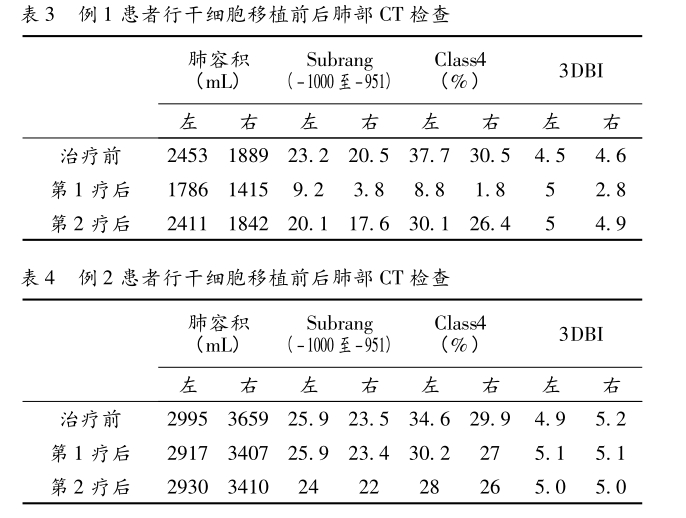

統(tǒng)計(jì)分析結(jié)果從表1、表2可看出對(duì)比治療前后的傳統(tǒng)肺功能檢查提示 FEV1 、FEV1 /pred( % ) 指標(biāo)無(wú)明顯好轉(zhuǎn),而生活質(zhì)量評(píng)分較治療前改善。

從表3、表4提示,CT 值在-1000 至-951 比例有所下降,Class4( % ) 亦明顯下降,故肺氣腫較治療前好轉(zhuǎn)。

綜上所述,研究中有2例慢性阻塞性肺疾病在應(yīng)用重組人粒細(xì)胞集落刺激因子動(dòng)員干細(xì)胞治療2~3周期后,三維CT測(cè)量肺功能指標(biāo)有所改善。

結(jié)論:重組人粒細(xì)胞集落刺激因子動(dòng)員干細(xì)胞治療慢性阻塞性肺疾病是一種安全有效的方法,值得臨床推廣。